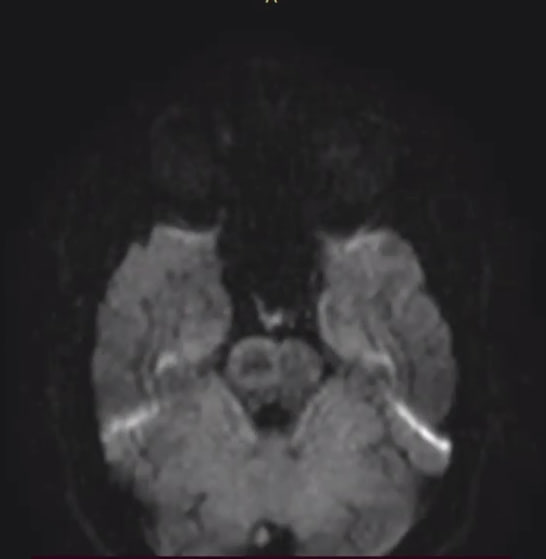

image.png 108Кб, 974x267

974x267

>>1628567

>>1613491 →

Посетил второй раз центр рассеянного склероза с результатами МРТ. Диагноз подтвердился, хотя внутри я все еще надеюсь, что это не ОНО.

Легкая головная боль прошла за это время, но упадок сил и сонливость никуда не делись.

Не могу понять, ухудшается ли у меня координация движений или стагнирует, но мне кажется, что я стал меньше пользоваться правой рукой.

Днем одолевает жуткая сонливость, не покидает ощущение воспаленности внутри, как на начальных стадиях ОРВИ, при этом у меня нет повышенной температуры, сложно сфокусироваться на одной задаче на работе, еще сложнее переключаться между задачами или думать и говорить.

Хотя я сплю в рабочие дни по 5 - 6 часов, но предыдущие три года жизни в таком ритме не вызывали у меня таких больших проблем.

Хотел бы я как-то если не восстановиться, то хотя бы убрать усталость, сонливость и ощущение воспаленности...

Есть тут еще анонимы с РС? Как поддерживаете себя?

Я еще позапрошлой зимой думал о том, что регулярный сон в 5 - 6 часов на фоне хронической депрессии ни к чему хорошему не приведет, а теперь диагноз заставил еще больше заняться самокопанием и ощущением того, что я многое не успел в жизни.

Аноним 09/07/25 Срд 18:57:40 1630672 178

>>1630672

Конечно нет, как у типичного офисного планктона, сутулость и искривление позвоночника в одну сторону. Но как это связано с сабжем?

Аноним 14/07/25 Пнд 21:54:55 1631631 186

>>1631629

Потому что от убитой осанки тоже могут быть такие симптомы. Но вообще, если тебе поставили диагноз, то ты лучше ему верь, а не мимокроку с харкача.